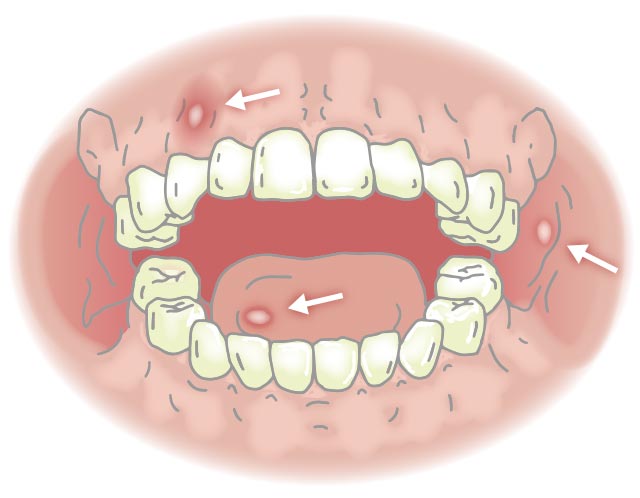

もっとも多く見られる口内炎アフタ性口内炎とは?八潮の歯医者 - LeaLea歯科・矯正歯科クリニック。

画像・症例写真あり アフタ性口内炎セルフチェックのポイント・治療法歯・口の病気All About。